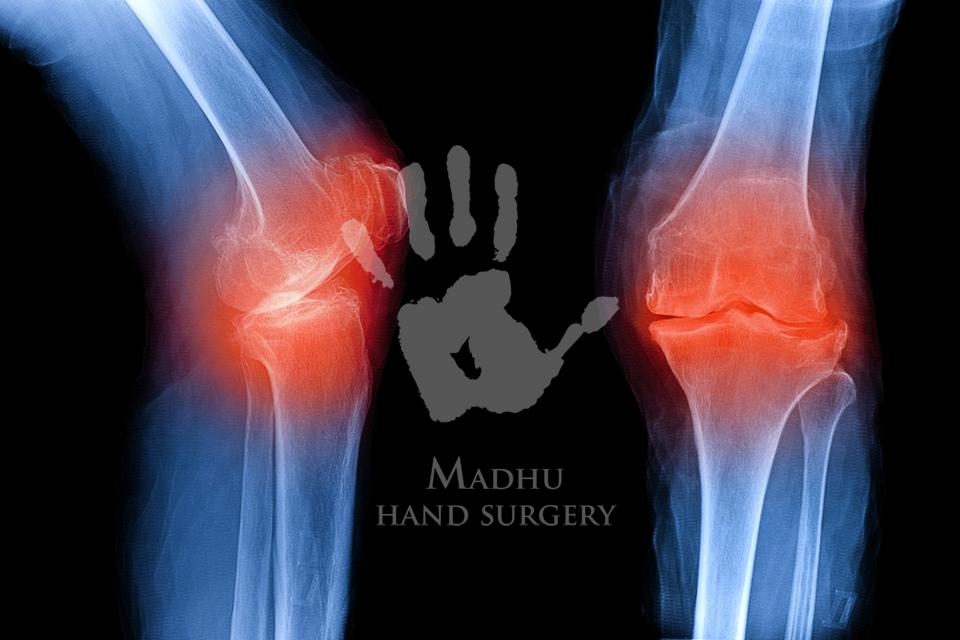

X-ray:

Knee X-Ray

To detect fractures, arthritis, bone spurs, or joint space changes.